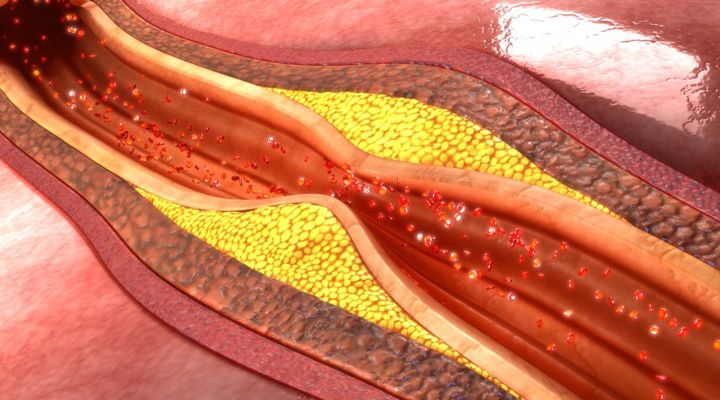

Barely Escaped Death